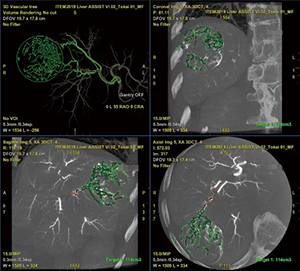

コーンビームCTデータ(以下,CBCT)を用いたAFDとして,弊社では,2012年に“FlightPlan for Liver(以下,FPFL)”を世界に先駆けて市場投入し,弊社製3Dワークステーション「Advantage Workstation」にて使用可能となった(図1)。

図1 Advantage Workstation VS7

■AFDの進化:“Liver ASSIST V.I.”と“Embo ASSIST”

その後,FPFLは,Liver ASSIST V.I.というアプリケーションに進化を遂げた。FPFLでは1つの結節にしか対応できなかったが,Liver ASSIST V.I.では同時に12個の結節まで栄養血管自動探索が可能となり(図2),加えて,“Virtual Injection(V.I.)”という,マウス操作によるカーソル位置の変更で血管の連続性をリアルタイムに確認できる機能も加わった(図3)。

図2 Liver ASSIST V.I.

本アプリケーションでは,栄養血管を探索するまではLiver ASSIST V.I.とまったく同様であり,腫瘍濃染をターゲットとして候補となる栄養血管の自動探索,各断面画像との並列表示&カーソル連動,そして,Virtual Injectionを用いた血管連続性の確認を行うことができる。